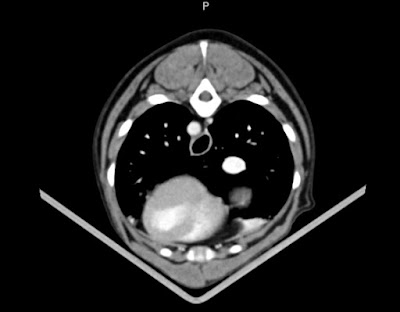

診所有隻光碟俾返媽咪, 但媽咪點識睇呢. 做記錄啦.